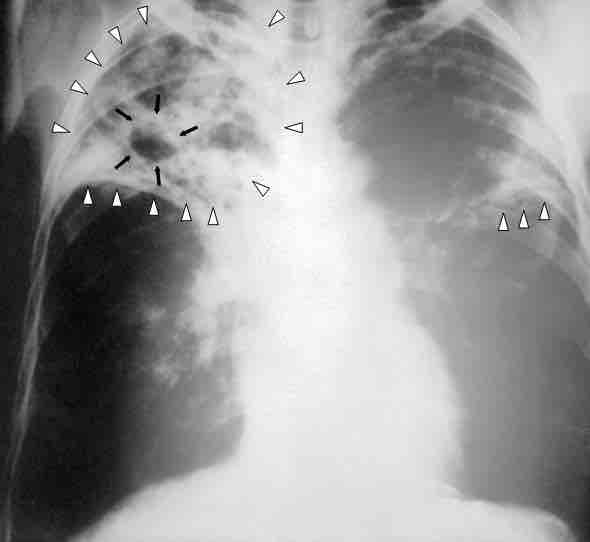

Chest x-ray of a patient with tuberculosis.

In this chest X-ray of a person with advanced tuberculosis, the infections in both lungs are marked by white arrowheads and the formation of a cavity is marked by black arrows. The boundary between contagious and non-contagious infectious diseases is not perfectly drawn, as illustrated by tuberculosis, which is clearly transmissible from person to person, but was not classically considered a contagious disease.